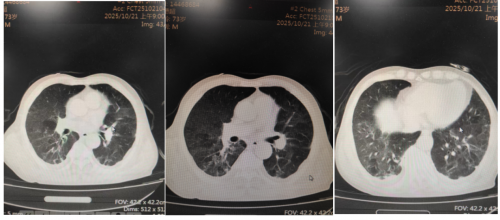

胸部CT平扫(2025.10.27):

10月28号出院,回当地医院随诊。